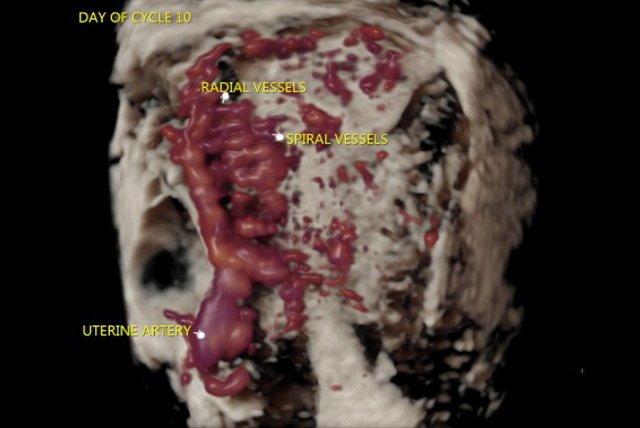

✔️ Endometrial Receptivity Study

✔️ Ultrasound assessment to plan management of uterine fibroids, uterine anomalies by 2D / 3D / Power Doppler Study

✔️ Doppler Flow studies